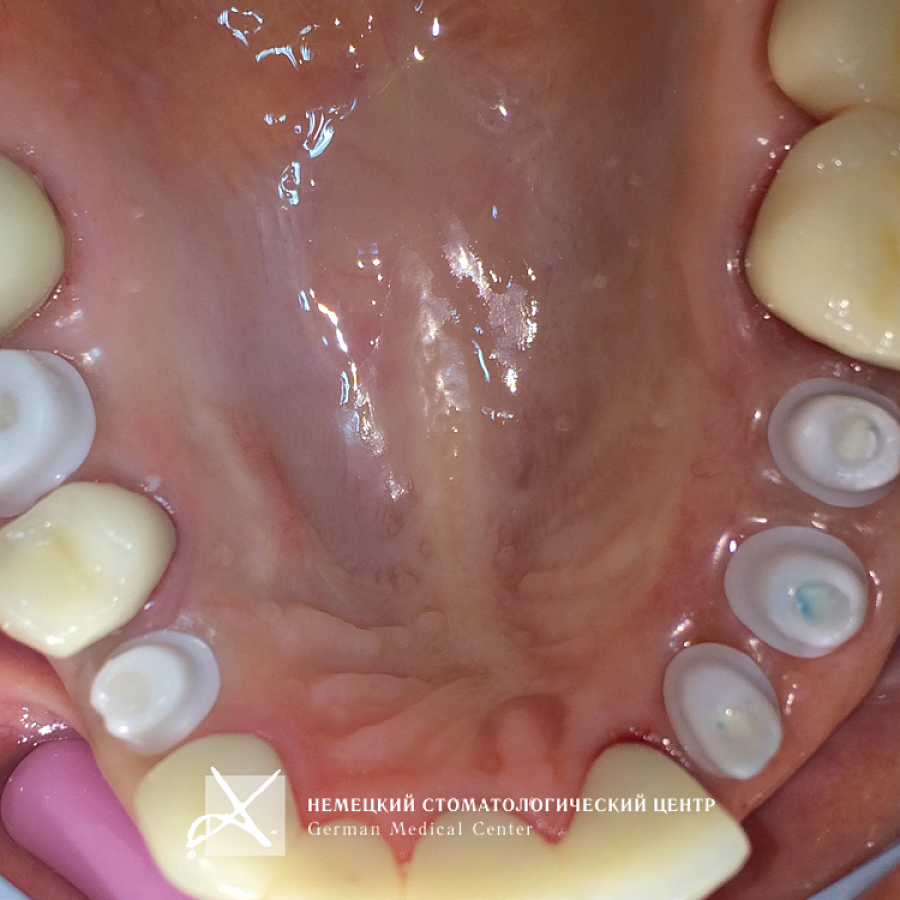

Пациентке проведено полноценное восстановление зубных рядов конструкциями с опорой на зубы и имплантаты. Коронки и абатменты изготовлены из диоксида циркония. Во время подготовительных мероприятий пациентка пользовалась временными конструкциями.